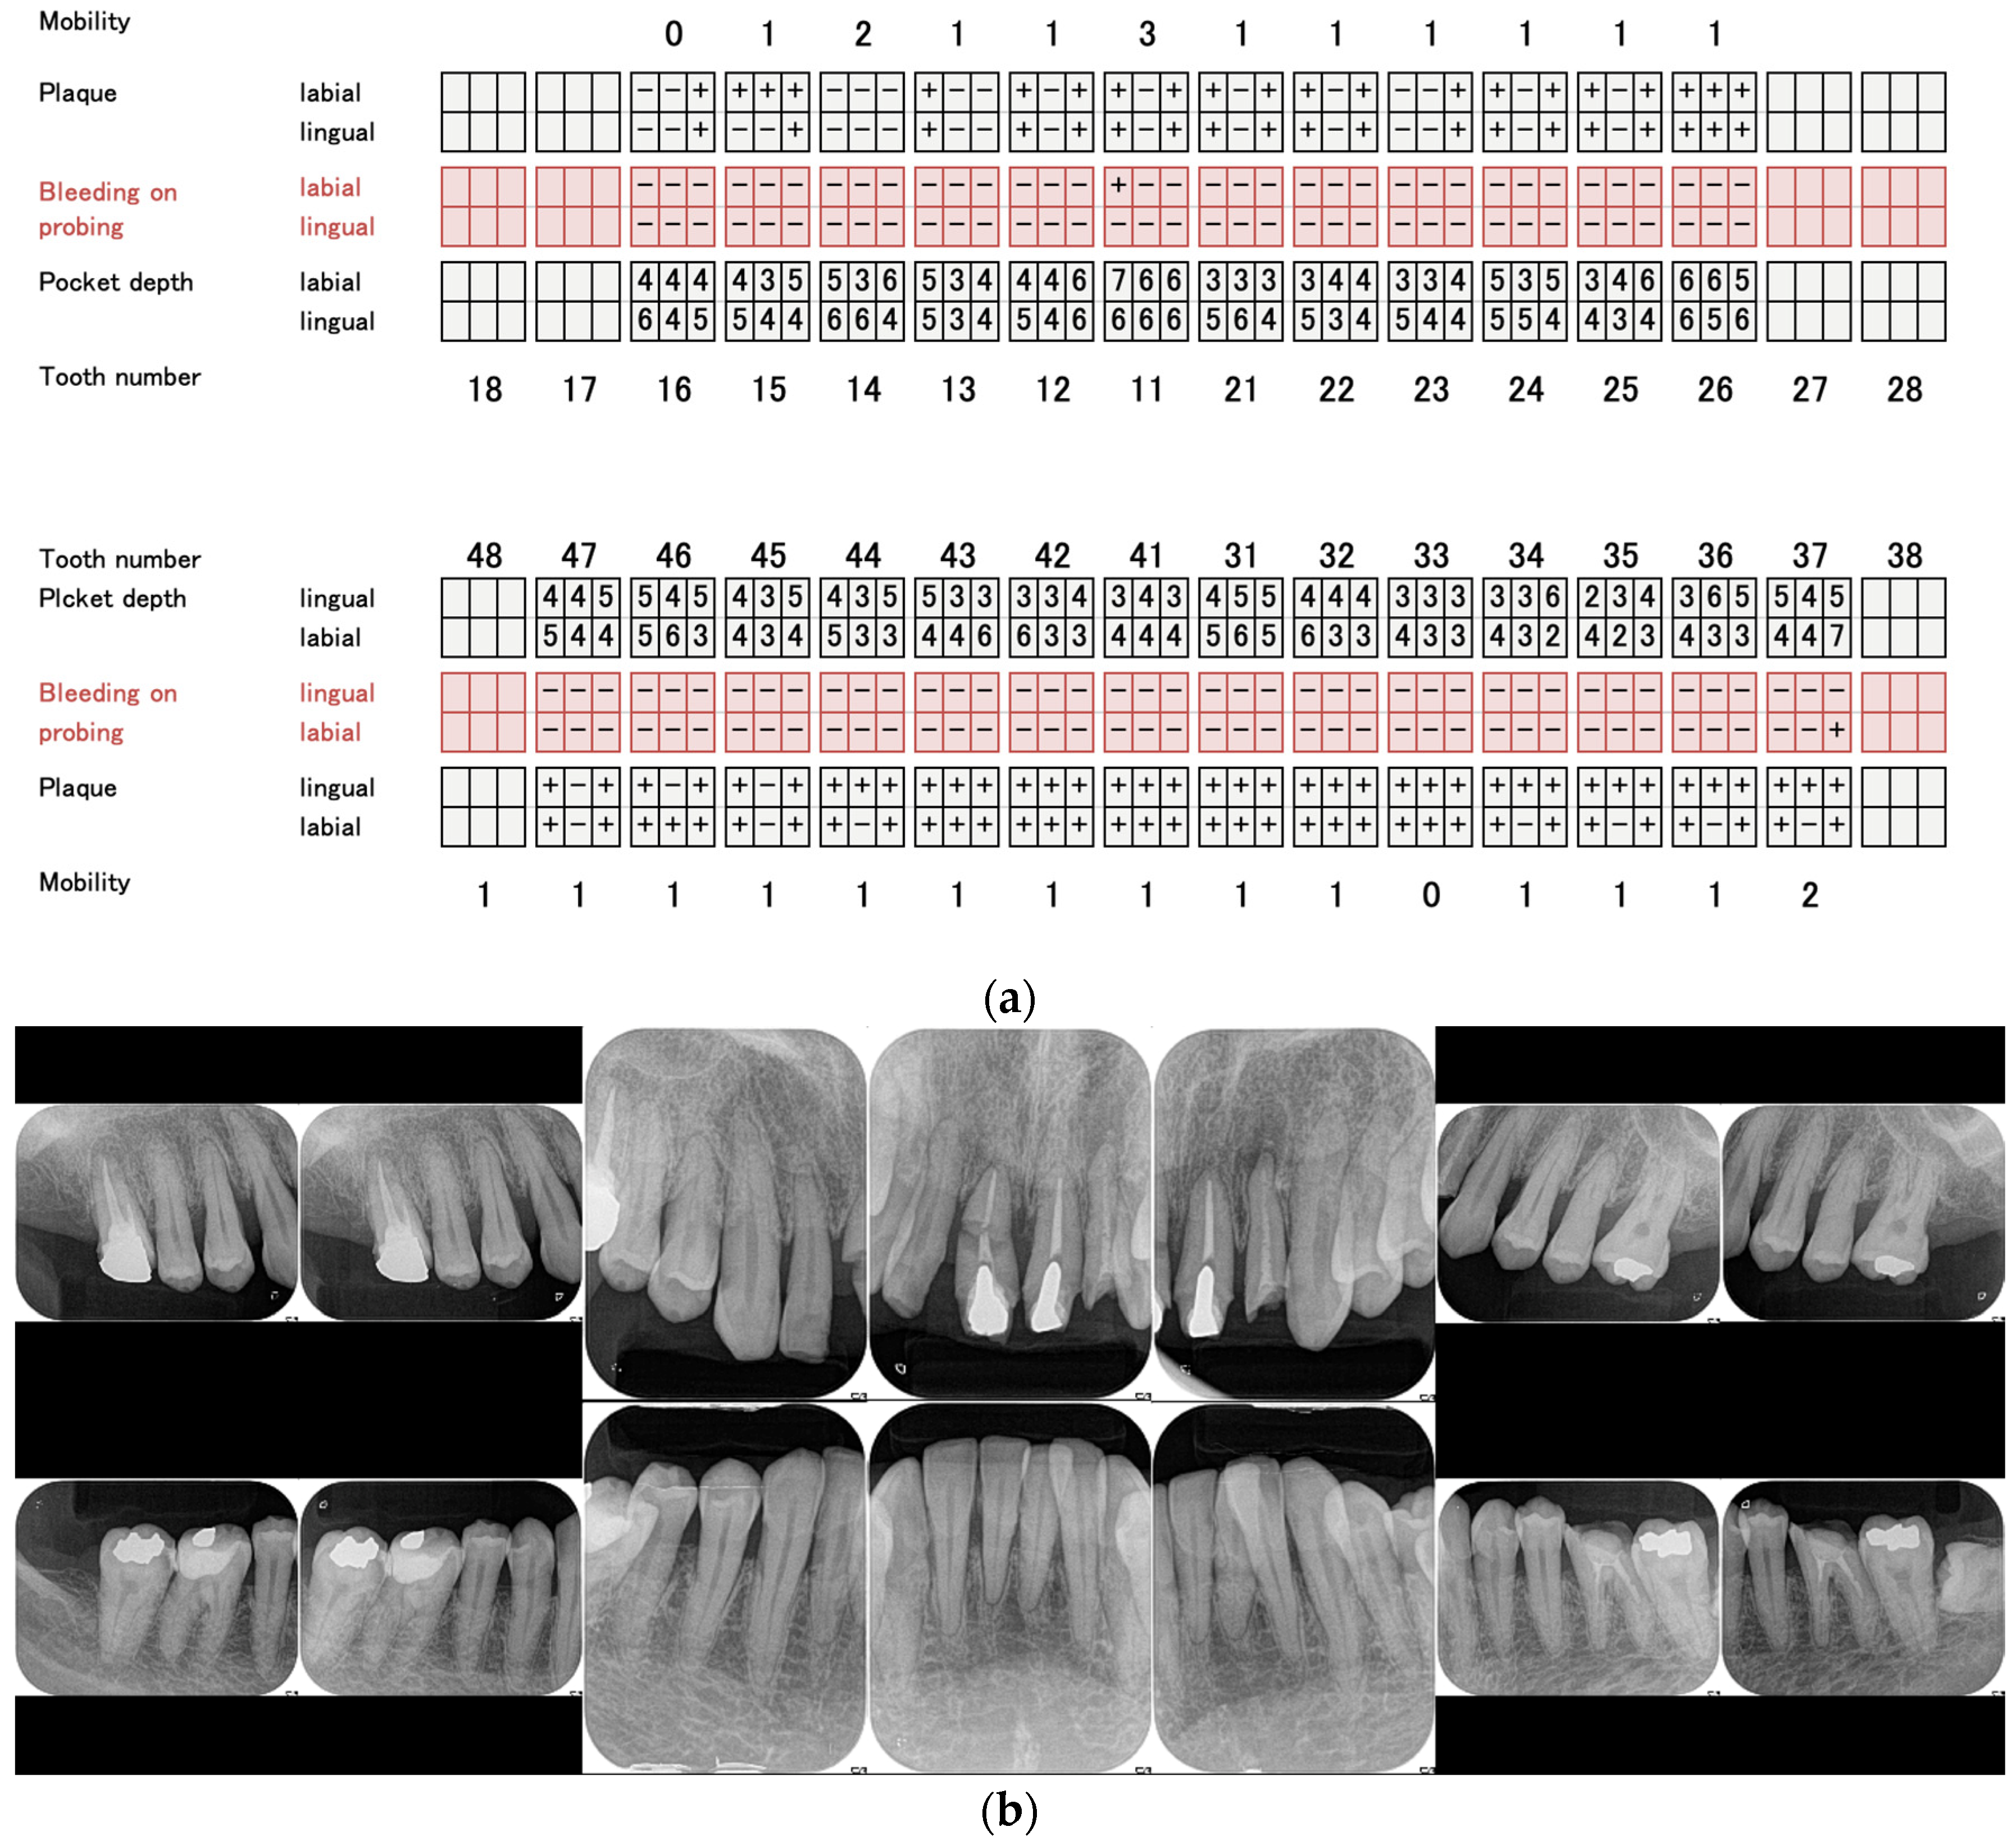

• Determination of the incisal edge position and virtual occlusal plane using lateral cephalometry (Figure 4a);

• Determination of the anterior–posterior positioning of the anterior teeth using the McNamara line (Figure 4b);

Figure 4. Determination of implant placement position using lateral cephalometry. (a) The incisal edge position and the virtual occlusal plane were determined using lateral cephalometry. (b) The anterior–posterior positioning of the anterior teeth was determined using the McNamara line (red line).